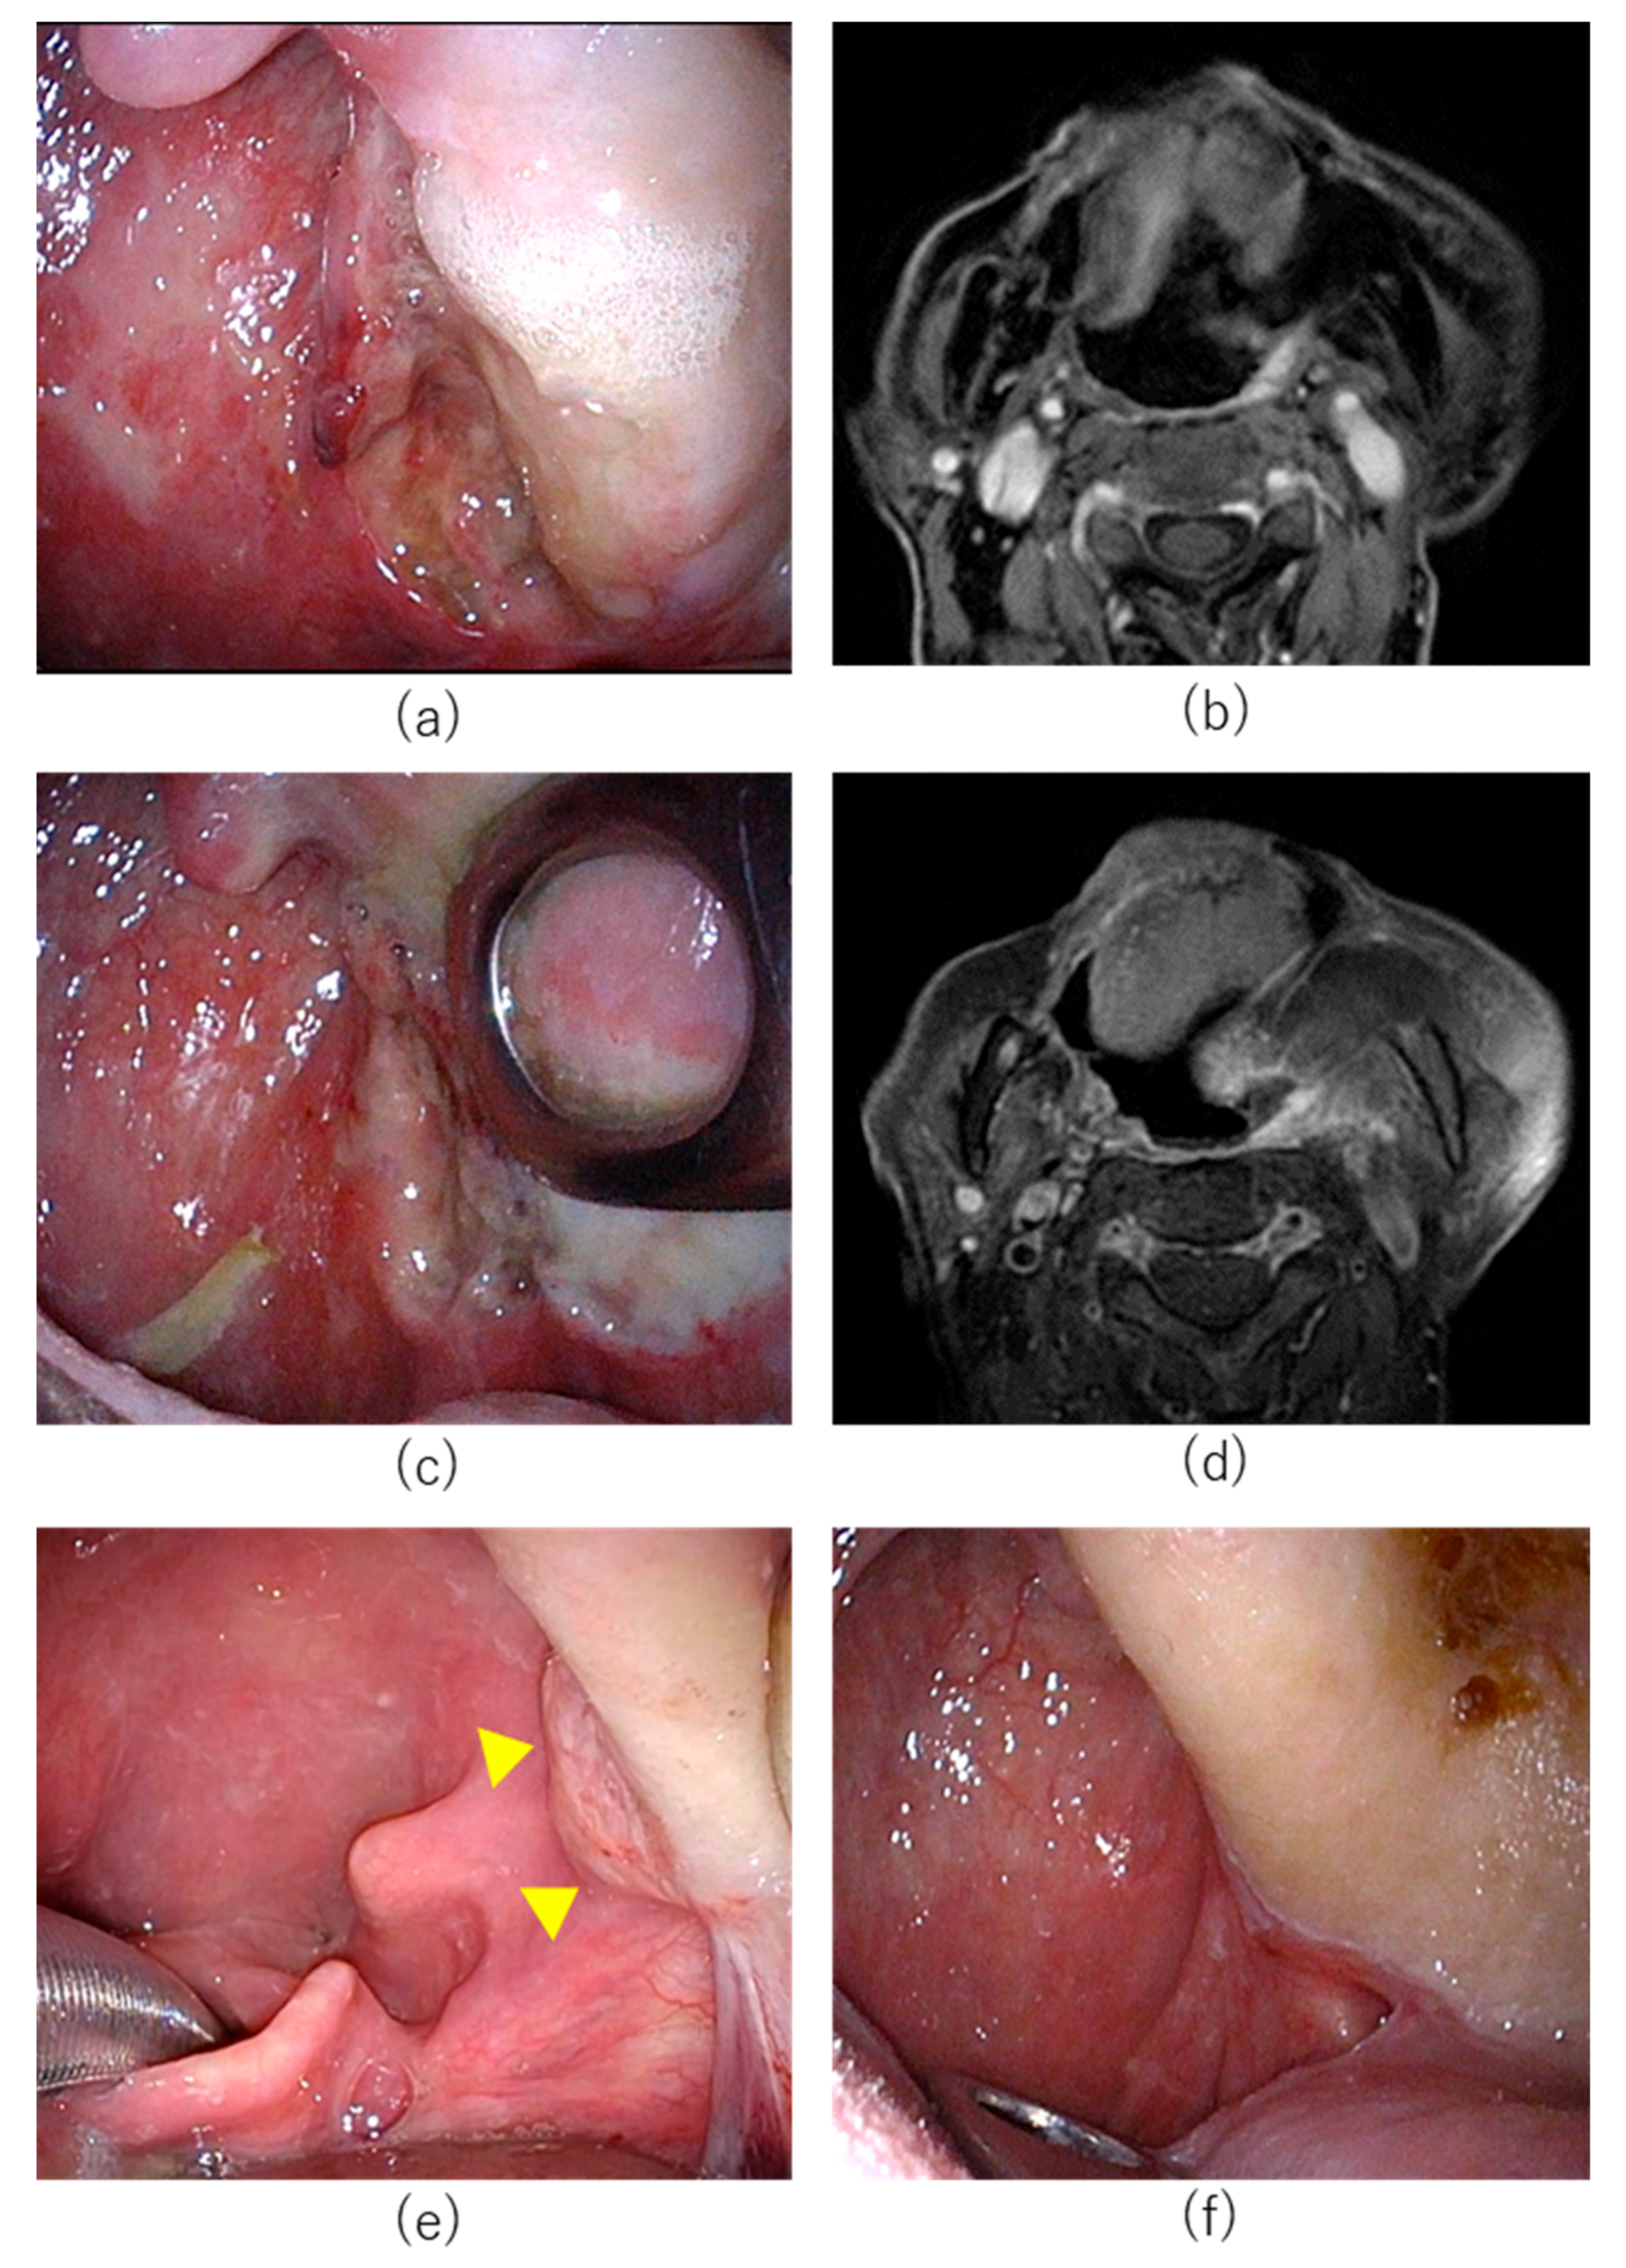

7.1. Case 1

7.2. Case 2